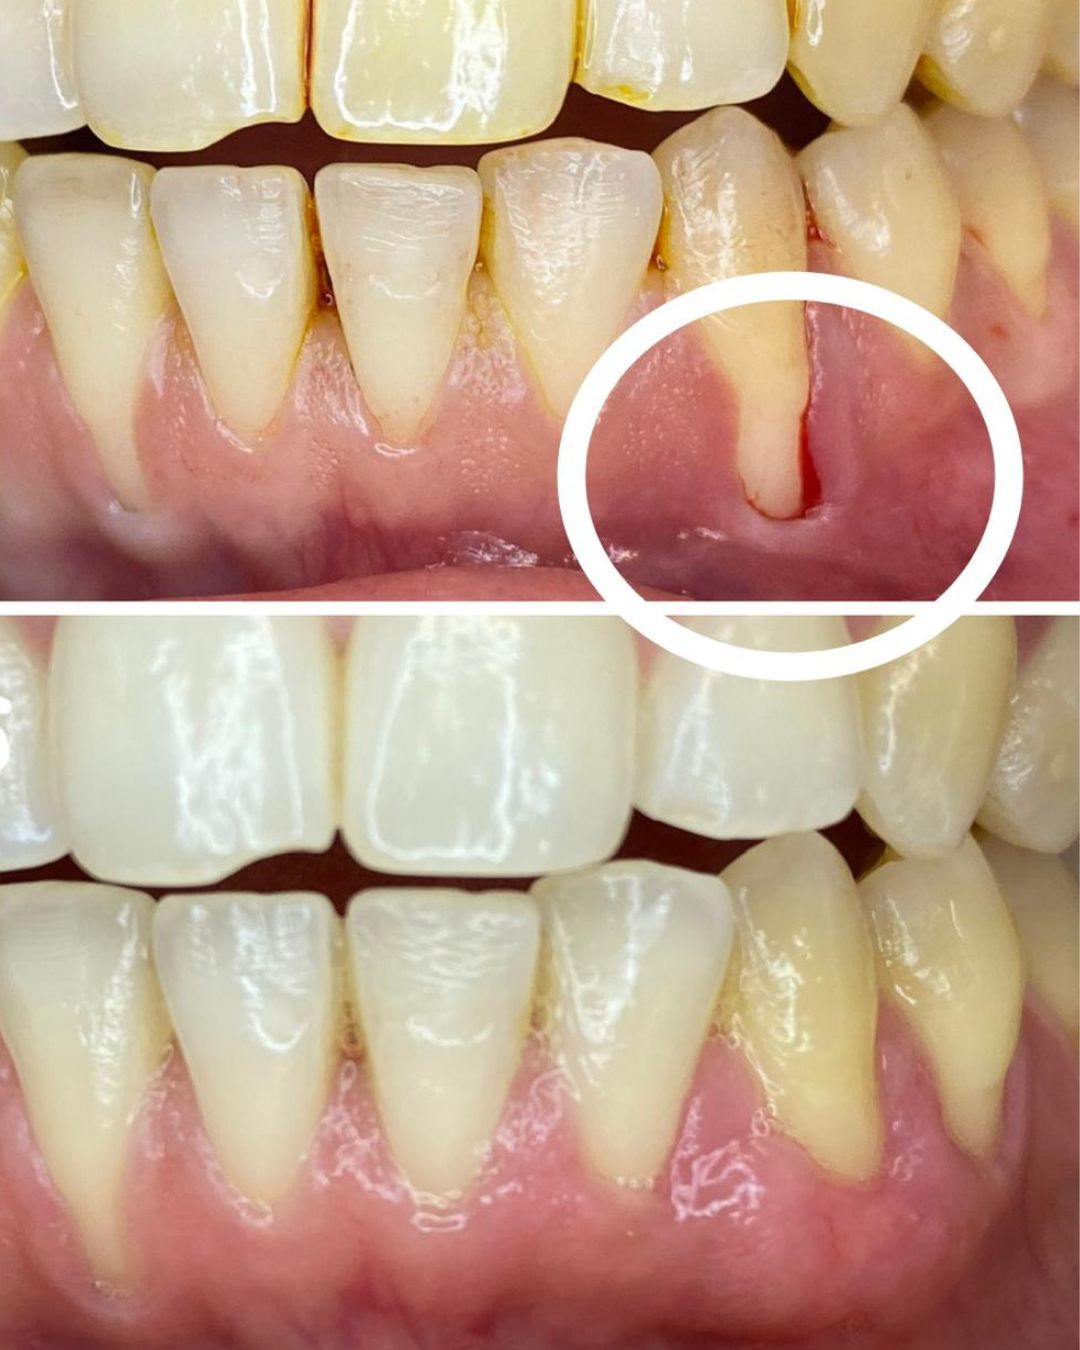

Volver a sonreír sin pensarlo.

No es magia. Es planificación digital, coronas de cerámica de primera calidad y el Método Gnadent. El paciente de estas fotos recuperó su sonrisa — y la libertad de mostrarla.

Casos Antes y Después

Pacientes reales, resultados reales. Desliza para explorar.